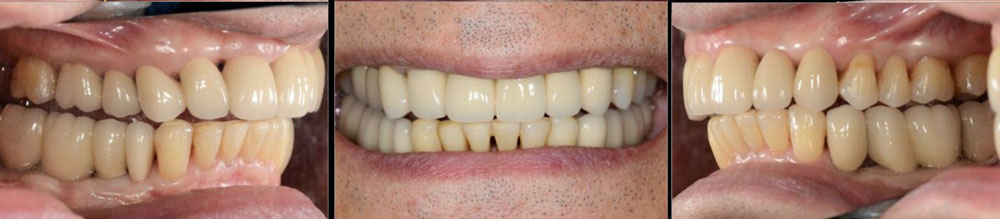

インプラント治療 咬合治療 補綴治療 GBR 矯正 精密根管治療 歯周病治療

治療後01

治療後02

治療後03

治療後04